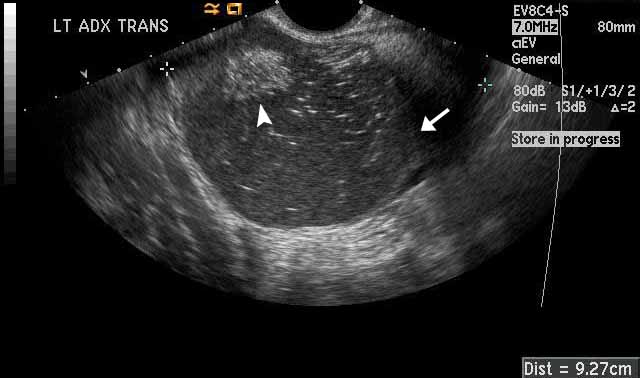

Dermoid

Image 2

The left adnexal dermoid cyst has both fat and fluid components as well. The white arrowhead points towards an echogenic fat component. The white arrow points toward a fluid-fluid level that separates simple from complex fluid within the cyst. The echogenic, or white, dots and dashes that you see within the cyst represent hair within the cyst. This finding is known as a “dermoid mesh. “ |